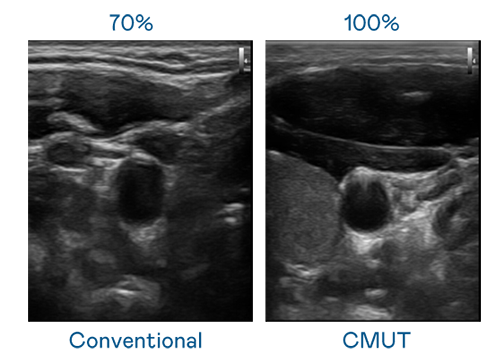

CMUT 技術是一種用電容式微機電元件來產生超音波訊號的技術。與傳統 PZT 壓電式技術相比,CMUT 頻寬增加 30%,更寬頻的超音波訊號讓影像解析度大幅提升,是實現高影像品質醫療超音波掃描、促進精準醫療發展的關鍵技術。

大頻寬帶來超清晰影像

超音波影像的解析度高低,首先取決於探頭能發出的訊號頻寬。德扑之星 CMUT 可提供高清晰的超音波訊號,提供高頻寬、高靈敏度、影像紋理細節更高的超音波影像,協助醫護人員縮短影像判讀時間及利用精準的醫療影像進行診斷。